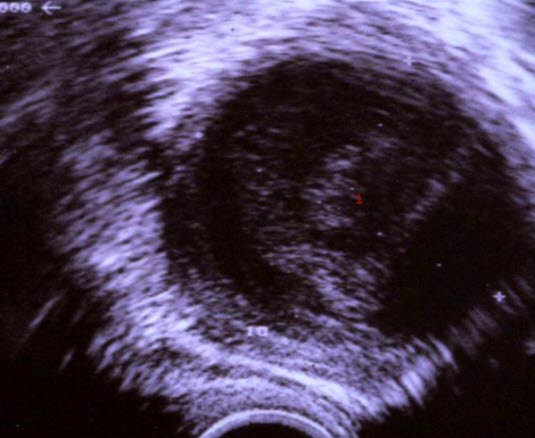

Tubo-ovariell abscess

1. Abscess, pussfyllt hulrom